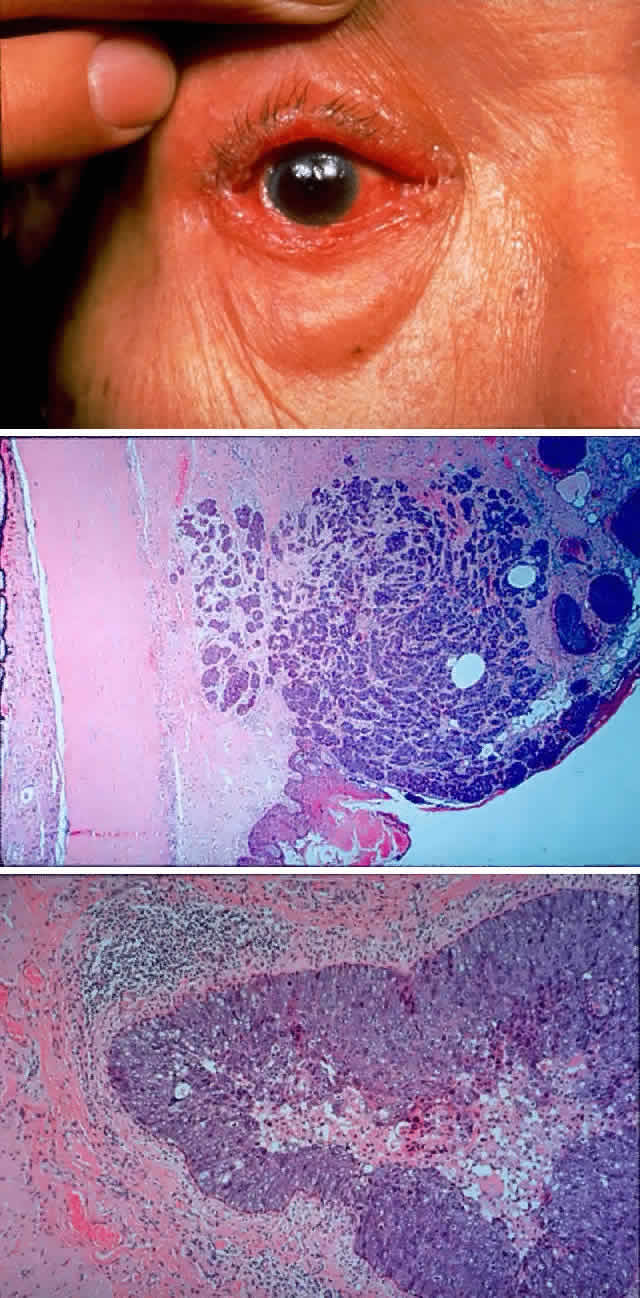

Primary acquired melanosis is typically a lesion of middle-aged whites and, along with malignant melanomas, are extremely rare in the younger population. In fact, McDonnell and colleagues109 found most conjunctival melanocytic lesions in patients less than age 20 to be nevi (92%), with infrequent occurrences of racial or primary acquired melanosis (4%) or malignant melanoma (4%). The natural history of primary acquired melanosis begins with the development of superficial epithelial pigmentation, with a characteristic peppered distribution of variegated pigment. These lesions can evolve over many years, extending in a radial fashion over larger areas of conjunctiva and skin. In addition, they may wax and wane over time. Ultimately, nodular melanomas may arise within primary acquired melanosis lesions, proceeding to invade deeper tissues and metastasize (Fig. 11). Biopsy of primary acquired melanosis lesions may help to predict the ones that are prone to progression. Folberg and associates110 found that primary acquired melanosis with cytologically atypical melanocytes progresses to melanoma in 46% of cases, whereas primary acquired melanosis without atypia does not progress to melanoma.

Fig. 11. A 61-year-old white man noted a pigment spot in the medial canthal area of his left eye associated with intermittent subconjunctival hemorrhages lasting 6 months. On examination, there was a raised, pigmented lesion in the lower medial conjunctiva (A) measuring 20 mm across the base, with a central, pale, telangiectatic nodule 6 mm thick noted on lateral gaze (B). There was extension into the upper medial fornix and laterally in the lower fornix. There was no evidence of preauricular, submandibular, or cervical lymphadenopathy. A clinical diagnosis of conjunctival melanoma arising in primary acquired melanosis (PAM) was made. Conjunctival biopsy revealed invasive melanoma (C and D) (H & E, × 80 and × 200, respectively) arising within PAM type IB (E) (H & E, × 200). A total exenteration and split-thickness skin graft from the anterior thigh were performed, and the patient was disease-free at 6 months' follow-up.

Malignant melanomas arising from nevi usually appear as a change in known pigmented lesions of the conjunctiva, but it may be impossible to establish a clear clinical history of a preexisting history of nevus. At the time of excision of a melanoma, however, nevoid rests are seen histologically in about one third of cases and are noted in about one quarter of melanomas in primary acquired melanosis. Development of a melanoma from a nevus may be heralded by increasing nodularity, variegated pigmentation, bleeding, or inflammation.

Melanomas arising de novo in conjunctiva parallel the so-called nodular melanoma of skin in that a clinically and histologically recognizable radial growth phase is not noted. Epibulbar melanomas arising de novo can be ulcerative, amelanotic, papillary, or fungating. It is important to be aware of the possibility of satellite lesions in the conjunctiva and local lymphatic spread, which should be sought carefully on a prospective basis.

In a recent clinicopathologic study of 256 cases of conjunctival melanoma, Paridaens and colleagues111 found 5- and 10-year survival rates of 83% and 69%, respectively. The following prognostic factors associated with a higher mortality are listed in increasing order of mortality risk111:

Two-fold risk: Tumors in unfavorable locations (e.g., palpebral conjunctiva, fornices, plica, caruncle, lid margins)

Three-fold risk: Mixed cell types compared with pure spindle cell types

Four-fold risk: Histologic evidence of lymphatic invasion; initial thickness greater than 4 mm for tumors in unfavorable locations only (Fig. 12)

Five-fold risk: Multifocal tumors in patients with lesions in favorable (epibulbar) locations only

Fig. 12. An 81-year-old white woman had been aware of a pigmented lesion in the left caruncular region for 18 months. It had gradually increased in size and had bled on several occasions. In addition, she was aware of a lump on the left side of her neck for 6 weeks. On examination, a large, nodular, pigmented medial conjunctival lesion associated with thickening and induration of the tarsal conjunctiva was noted, as was a nodular satellite lesion in the temporal aspect of the inferior fornix due to local lymphatic spread (A). There was lateral displacement of the globe and some limitation of abduction. Axial CT scan demonstrates the irregularly shaped mass in the anterior orbit involving the insertion of the medial rectus muscle (B). The patient refused exenteration and underwent local resection, cryotherapy, mucous membrane graft, and radical neck dissection. Of 31 neck nodes removed, 2 were positive for metastatic disease. Nodular recurrence developed in her left jaw, and the patient died 1 year after presentation without evidence of local ocular recurrence. (Rootman J, Ragaz J, Cline R, Lapointe JS: Metastatic and secondary tumors of the orbit. In Rootman JR (ed): Diseases of the Orbit: A Multidisciplinary Approach, pp 405–427. Philadelphia, JB Lippincott, 1988.)

Understanding of the clinicopathologic characteristics of premalignant and malignant melanocytic lesions of the conjunctiva has advanced considerably in recent years.112 This increased recognition along with biopsy and treatment of potentially aggressive lesions should lead to decreased morbidity and mortality. The primary treatment for conjunctival malignant melanoma is wide surgical excision combined with cryotherapy.113 Even extensive conjunctival disease is amenable to removal of the nodular component and repeated local treatment with cryotherapy. Lederman and co-workers106 reviewed a series of 184 melanomas of conjunctiva treated with radiotherapy and found that lesion site, macroscopic appearance, and type of lesion bear significantly on the type of treatment and likelihood of response. Limbal tumors arising from nevi respond well, nodular de novo melanomas respond poorly, and widespread malignant acquired melanosis responds less well than localized lesions.

Significant orbital invasion indicates the necessity for exenteration; however, subtotal exenteration can be carried out if there is no evidence of radial extension of the lesion to the skin of the anterior lid. Nodal involvement indicates widespread metastatic disease, but occasionally there have been cases in which lesions were restricted to regional nodes and cured by node resection.

Extrascleral extension occurs in 10% to 15% of patients with uveal melanomas118–120 and may present clinically as a visible anterior nodule, as proptosis in patients with known intraocular tumor (Fig. 13), with phthisis and unsuspected tumor, or as a mass in orbital recurrence. Orbital recurrence associated with hepatic metastasis has been described as late as 42 years after primary enucleation.121 Orbital extension may only become evident at the time of surgery; however, the use of ultrasonography and CT scan may lead to increasing preoperative detection of extrascleral nodules.

Fig. 13. A 65-year-old man presented originally with a right retinal detachment and secondary glaucoma due to a large choroidal melanoma. The patient refused enucleation and self-treated instead with herbal medicines and “health foods.” He presented again 6 years later with acute onset of proptosis associated with pain, periocular edema, erythema, and marked restricted ductions (A). CT scan revealed the intraocular tumor, with massive orbital extension and displacement of the globe anteriorly, downward, and laterally (B and C). He underwent lid-splitting exenteration and split-thickness skin graft from the anterior thigh. The gross specimen shows the massive orbital component of melanoma, which had extended from the posterior choroid through emissarial vessels (D). An area of predominantly spindle-shaped melanoma cells with scattered, heavily pigmented macrophages is shown (E) (H & E, × 200). (D and E courtesy of Valerie A. White, MD, Department of Pathology, University of British Columbia, and the Vancouver Hospital and Health Sciences Center.)